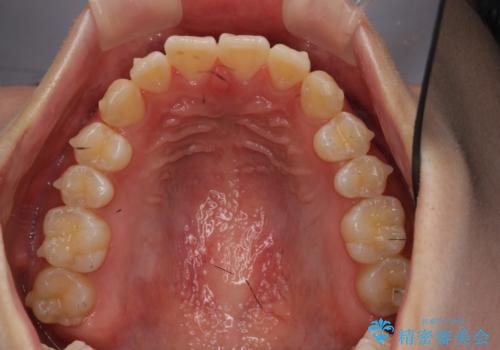

出っ歯 軽度のがたつき インビザラインで

- 20代女性

- インビザライン

- 奥歯を後ろに下げる処置をおこなっています。

前歯にオープンバイト気味の症状がありましたが、前歯を後ろに下げることでしっかりかませています。

前歯のずれも治り、しっかり下がりました。

前歯を下げるのに、顎間ゴムを使用していただいています。